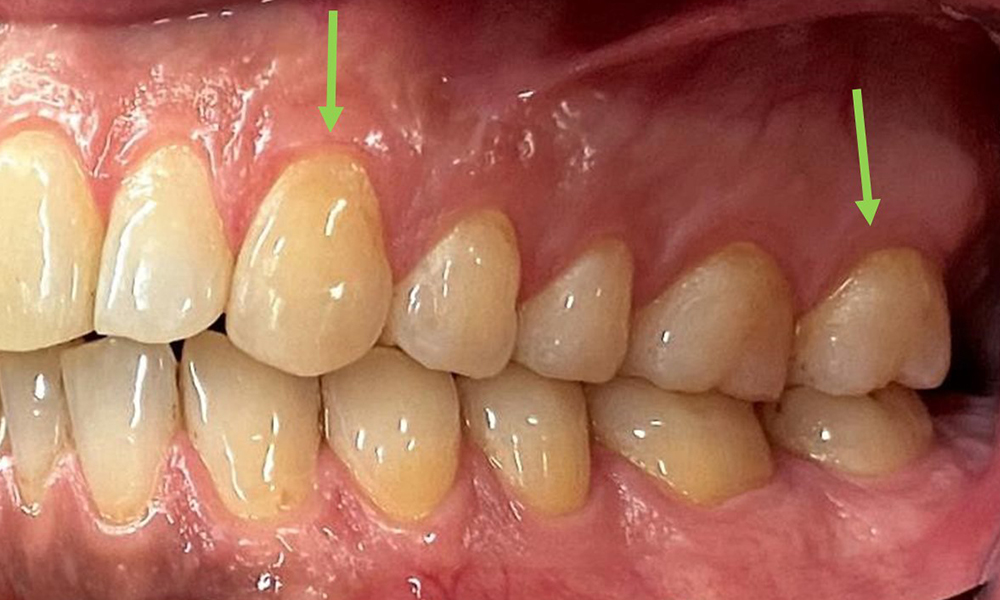

The patient has full dentition with a total of 28 teeth. There were noteworthy erosions and attritions. (Fig. 4, Fig. 5). Due to bruxism, the patient has been wearing a splint with an adjusted bite block at night for many years. The erosions were caused by long-term consumption of isotonic beverages. No periodontal bone loss or active caries were observed.

At 1 to 3 mm, the clinical probing depths were within the physiological range. Maxillary recessions of up to 1 mm were observed from 13 to 16 and 23 to 27. The BOP was 15%.